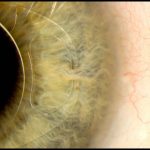

Intraocular lens ‘iris clip’

This image shows how an ‘iris clip’, also known as an artificial intraocular lens (IOL), is fitted onto the eye. An iris clip is a small, thin lens made from silicone or acrylic material, and has plastic side supports, called haptics, to hold it in place. An iris clip is fixed to the iris through a 3 mm surgical incision, and is used to treat conditions such as myopia (nearsightedness) and cataracts (cloudiness of the lens). This particular patient, a 70-year-old man, regained almost full vision following his surgery.

MARK BARTLEY, CAMBRIDGE UNIVERSITY HOSPITALS NHS FOUNDATION TRUST